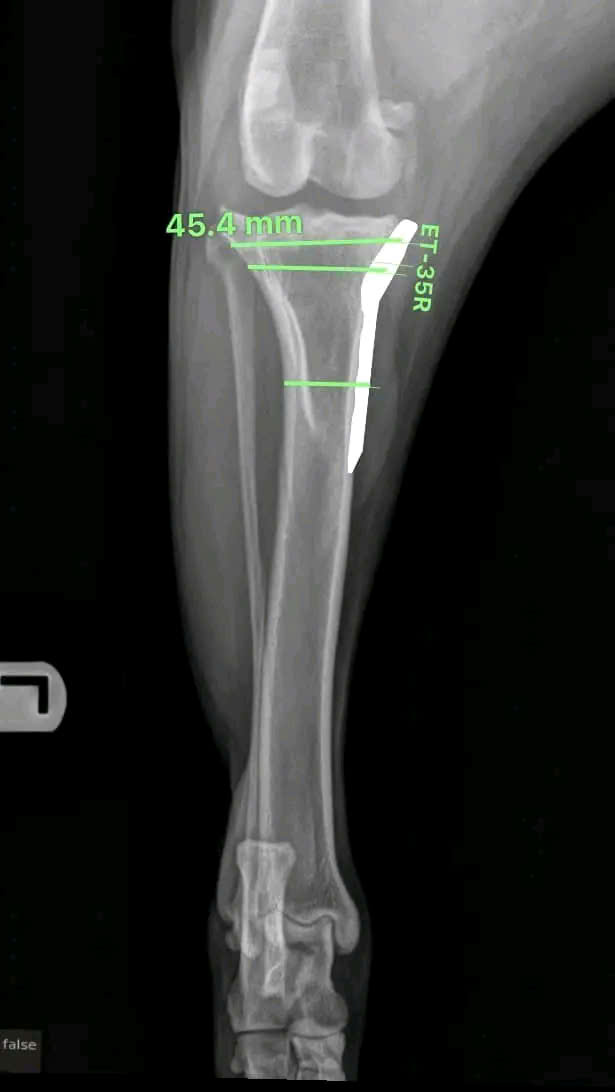

Hình ảnh thực tế

Khám phá không gian chăm sóc thú cưng chuyên nghiệp tại Bệnh viện Thú Y Gia Kiệm